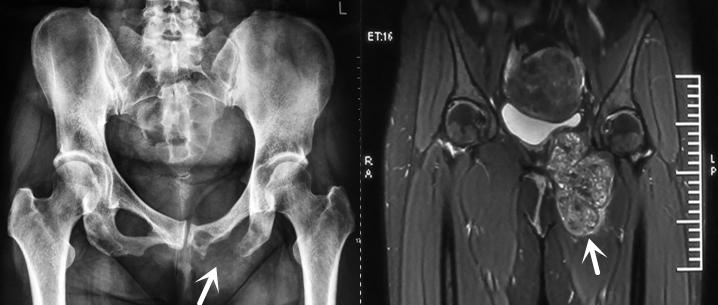

图中所示为该患者的骨盆巨大骨巨细胞瘤

该患者在当地医院检查时发现其左侧耻坐骨骨破坏严重,肿瘤已突破骨皮质,正向内上生长,挤压膀胱,向内挤压股动静脉、股神经。当地医生建议她到我院接受手术治疗。

患者在我院住院后接受病灶穿刺活检,检查显示部分组织退变,局部坏死碎骨组织。快速病理示:富巨细胞病变。根据患者影像学多房、肿瘤信号不均、穿刺肿瘤组织的质地及快速病理的结果,骨肿瘤科的专家们经讨论认为该肿瘤为III期骨巨细胞的可能性大,不排除骨肉瘤、骨转移癌。

经过详细的术前规划、精湛的术中操作,骨肿瘤科医疗团队圆满完成了这例解剖位置复杂、术中出血量多、临床罕见的耻坐骨骨巨细胞瘤手术,为患者切除了大小约为12×11×4cm的肿瘤。目前,患者的术后情况良好,能正常下地活动。术后7天病理结果回报示:富巨细胞肿瘤,结合临床及影像学符合巨细胞瘤。